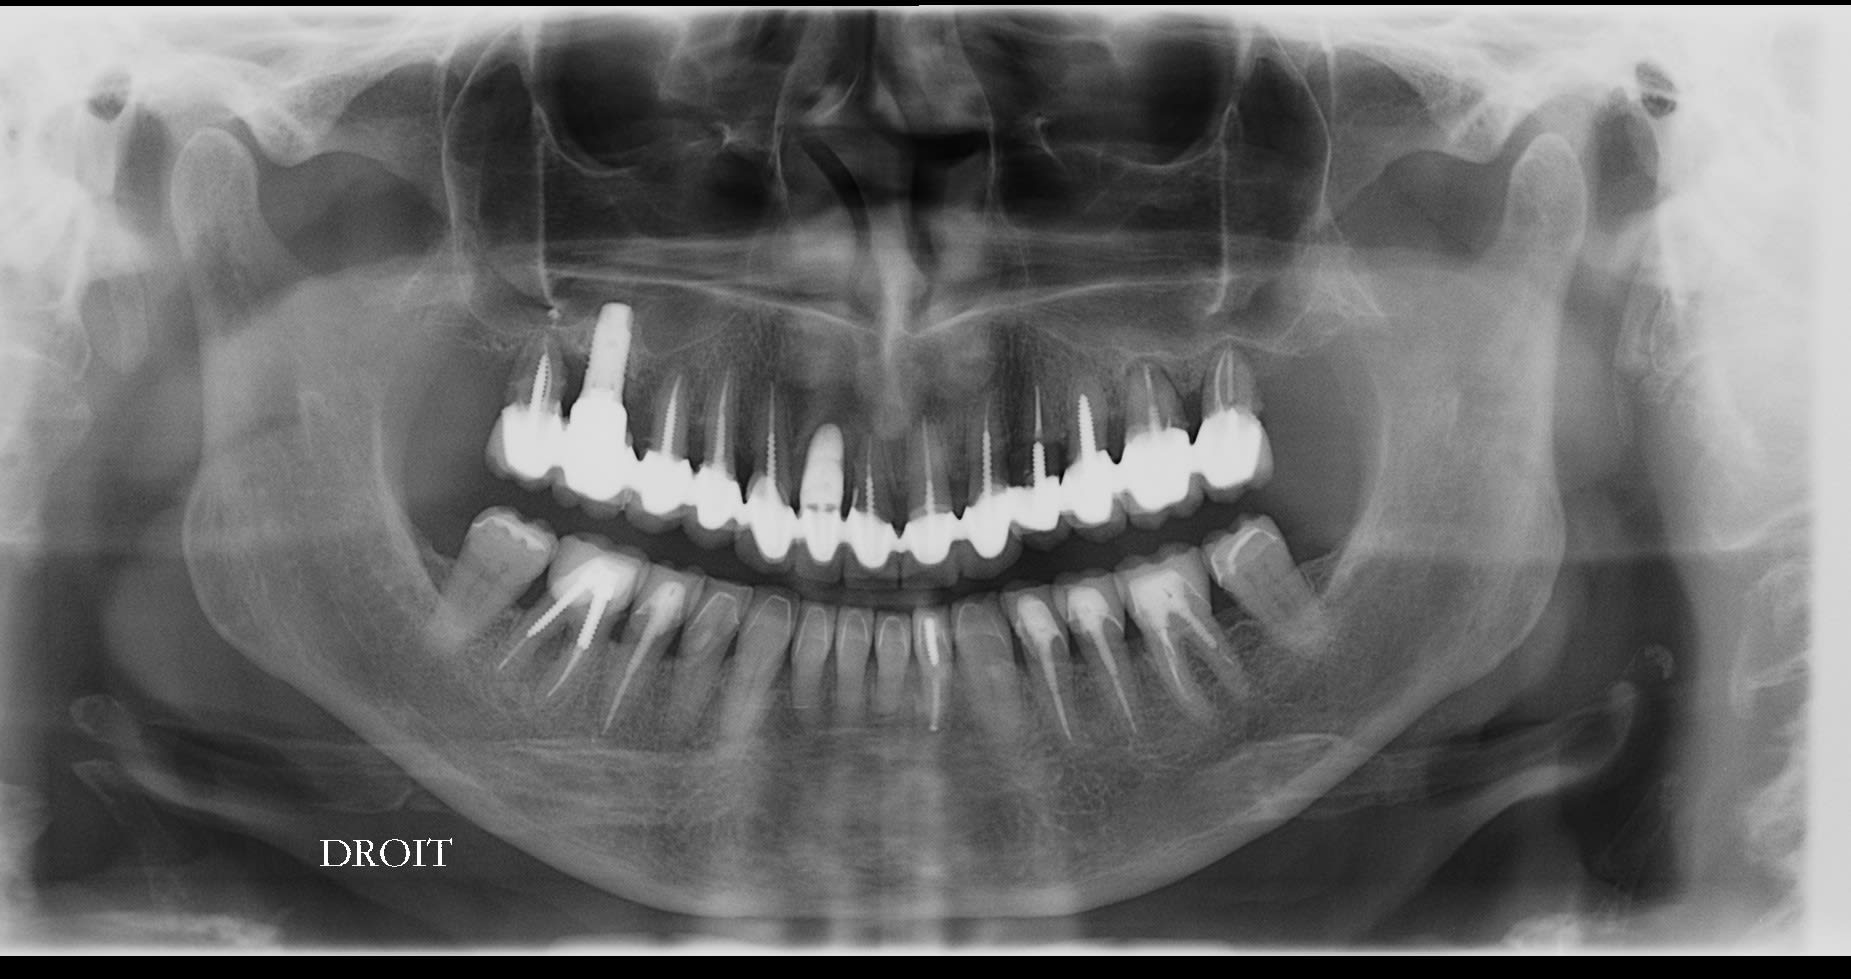

Bonjour à tous,

Voici comme prévu les photo du cas, j'ai pris les empreintes ce jour donc je posterais des photos des moulages dès que le proto les aura coulés !

Esthétique... Combler les diastèmes, teinte etc. et accessoirement pérenniser ses dents...

je suppose que le pt inter incisif n est pas au milieu de la figure , je me trompe ?

on dirait que le secteur 20 est parti à gauche , y compris la 11 , et qu a partir de la 11 le secteur 10 s est vestibulé . donc je confirme que tu ne peux faire le haut sans le bas .